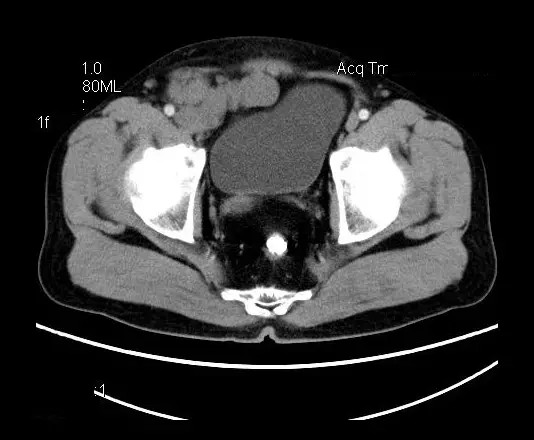

【影像表现】

盆腔右前侧及邻近腹股沟区可见多发大小不等的聚集生长的结节影,病灶呈软组织密度,边缘尚规整,分界尚清,增强扫描可见不均匀强化。膀胱局部受压,盆腔未见明显肿大淋巴结影。

“盆腔”多发性神经鞘瘤